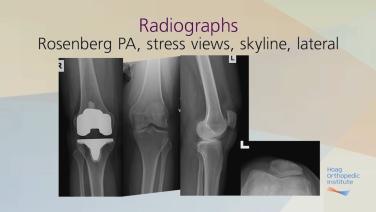

Pre-Operative Evaluation with Robert Gorab, MD